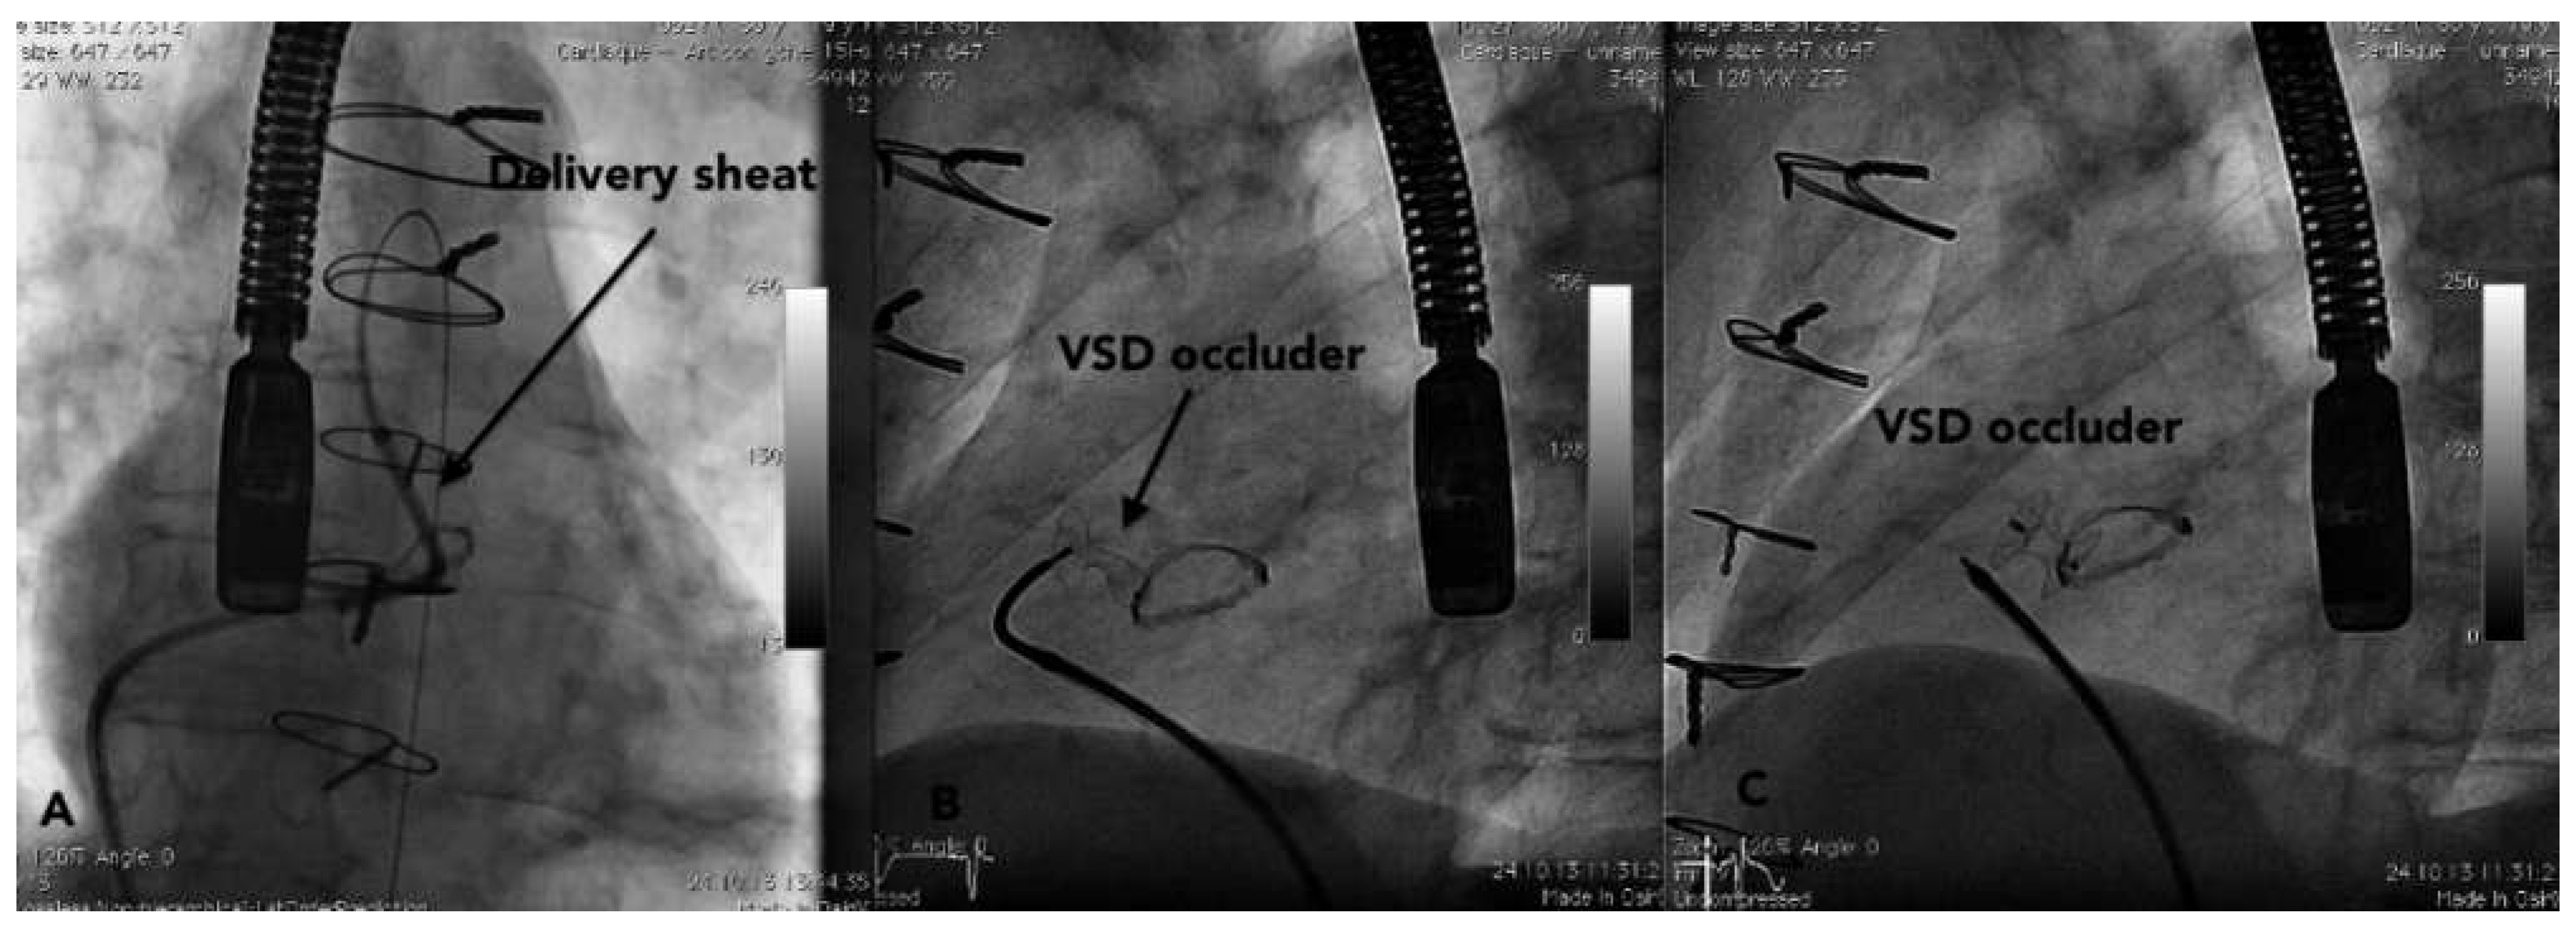

Case report